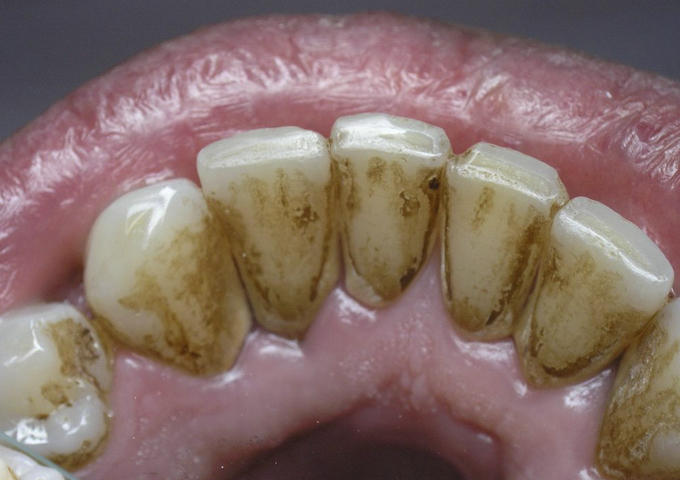

Неправильная чистка может привести к образованию зубного налета и тогда начинает образовываться зубной камень, затвердевший налет. Зубной камень может привести к разрушению зубов и заболеваниям десен. Поэтому его необходимо удалять, чтобы предотвратить другие серьёзные заболевания полости рта.

Мы представляем вам несколько домашних средств для удаления зубного камня и предотвращая его дальнейшего образования :